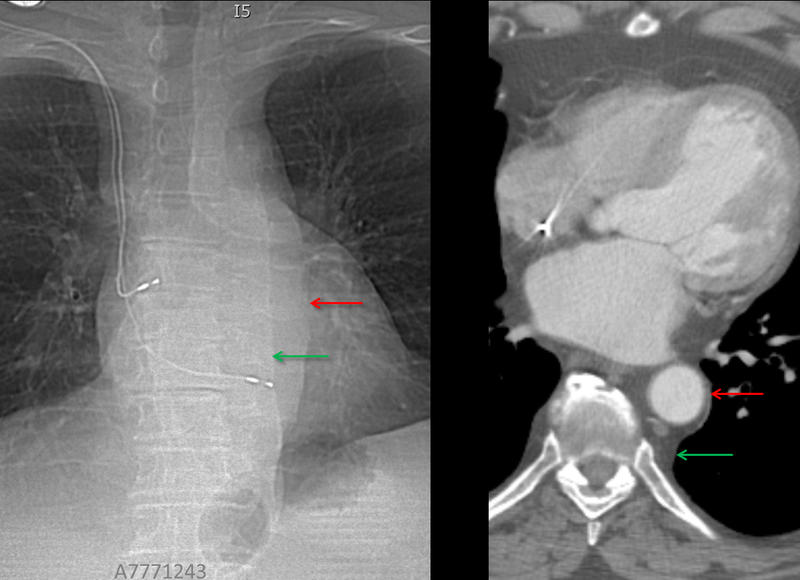

paraspinal interface